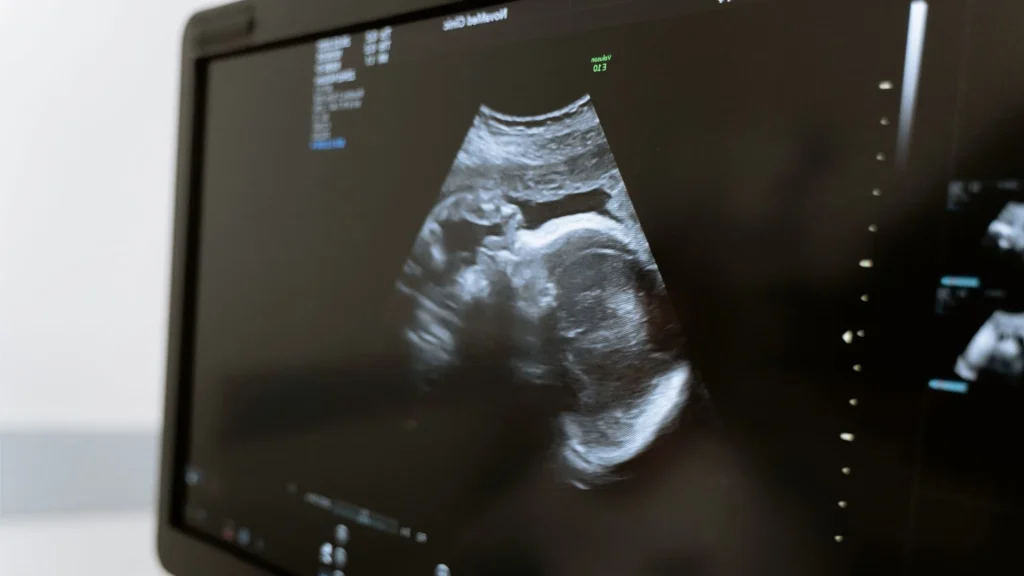

Dukungan untuk Pemeriksaan Kehamilan

Bidan di desa bisa menggunakan USG portable untuk memantau kehamilan ibu hamil. Ini membantu mendeteksi risiko sejak dini dan menurunkan angka komplikasi.